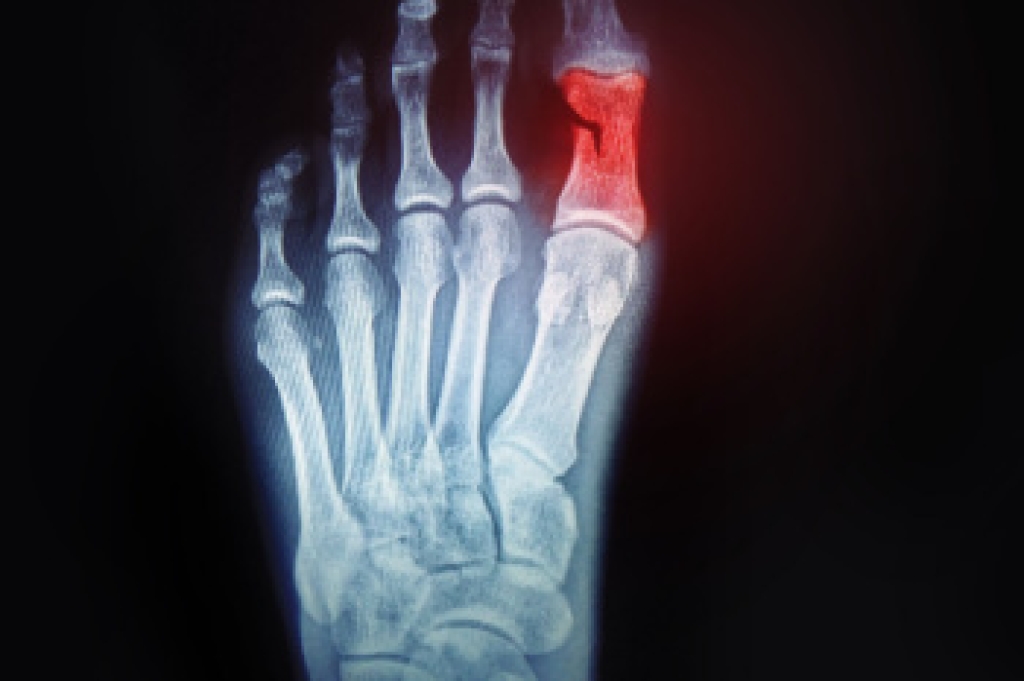

A toe fracture is a break in one or more of the small bones in the toes, usually caused by direct trauma, such as stubbing the toe or dropping a heavy object on the foot. These injuries are common and can vary in severity. Symptoms may include sharp pain, swelling, bruising, and difficulty in walking. In some cases, the toe may appear crooked or deformed. Risk factors include weak bone density, participation in contact sports, and walking barefoot in unsafe areas. A podiatrist can provide a thorough evaluation and determine the best treatment to ensure proper healing. If you think you may have fractured your toe, it is suggested that you consult a podiatrist who can accurately diagnose and treat this injury.

Although most people try to avoid foot trauma such as banging, stubbing, or dropping heavy objects on their feet, the unfortunate fact is that it is a common occurrence. Given the fact that toes are positioned in front of the feet, they typically sustain the brunt of such trauma. When trauma occurs to a toe, the result can be a painful break (fracture).

Severe toe fractures may be treated with a splint, cast, and in some cases, minor surgery. Due to its position and the pressure it endures with daily activity, future complications can occur if the big toe is not properly treated.